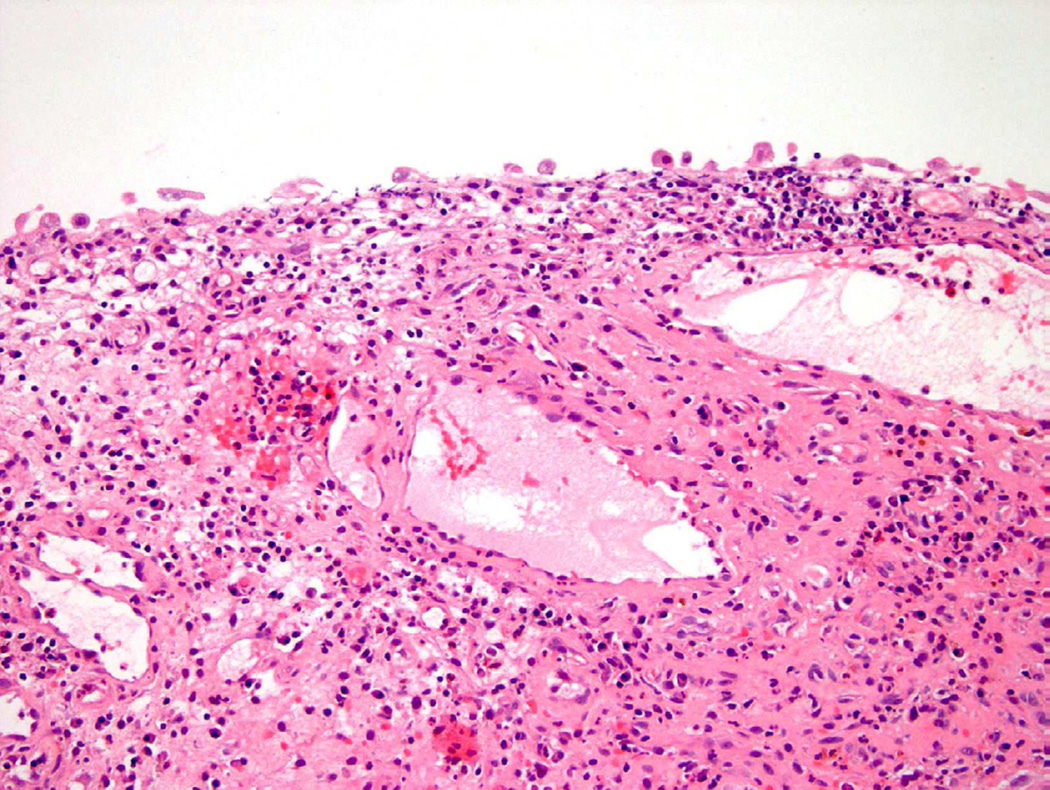

Acute and Chronic Cystitis

The most common cause of acute cystitis is infection, primarily but not restricted to, gram-negative bacteria11. Additional causes of acute cystitis include prior instrumentation, trauma, and catheterization. In the acute setting, inflammatory-mediated cell responses lead to an influx of neutrophils, lymphocytes, and macrophages within the urothelium and lamina propria of the bladder. Edema and vascular congestion are also common12. While reactive changes of the urothelium may not occur until the subacute or chronic inflammatory phase, pronounced inflammation can obscure underlying pathologic processes and make assessment extremely difficult for the pathologist, thus leading to a diagnosis of atypia. In the setting of chronic cystitis, a variety of changes can occur in the urothelium including denudation, ulceration, or hyperplasia. In addition to difficulties in adequately visualizing the specimen microscopically secondary to copious amounts of granulation tissue and/or fibrosis, reactive atypia due to a persistent inflammatory process can raise suspicion for dysplasia in the bladder8.

Polypoid Cystitis

Polypoid cystitis, a common variant of cystitis in the bladder, remains a challenging inflammatory lesion for pathologists and urologists alike13 (fig 7). On cystoscopy, the often exophytic growth pattern of polypoid cystitis may clinically resemble a papillary neoplasm. These lesions tend to appear in patients with a history of indwelling catheters, fistulas, chronic obstruction, or calculi. Microscopically, the lesion consists of large, bulbous outpouchings of the urothelial lining, with the lamina propria often quite edematous (Fig. 8)13. Over time, ongoing inflammation may produce scarring of the lamina propria leading to a more papillary-like appearance, as well as induce squamous metaplasia and reactive atypia14. In a 2008 study, 41 cases of polypoid cystitis that had been previously misdiagnosed as papillary urothelial neoplasia were re-reviewed13. Despite some mild atypia and mitotic figures in many of the cases, the cytologic features included uniform cell enlargement, similar vesicular chromatin patterns, and a single prominent nucleolus. Each of the 41 cases lacked definitive hyperchromasia and nuclear pleomorphism which are key criteria in differentiating benign, reactive lesions from neoplasia.

Figure 7.

Polypoid cystitis.

Figure 8.

Flat urothelial hyperplasia recognized as thickened urothelium with no atypia.